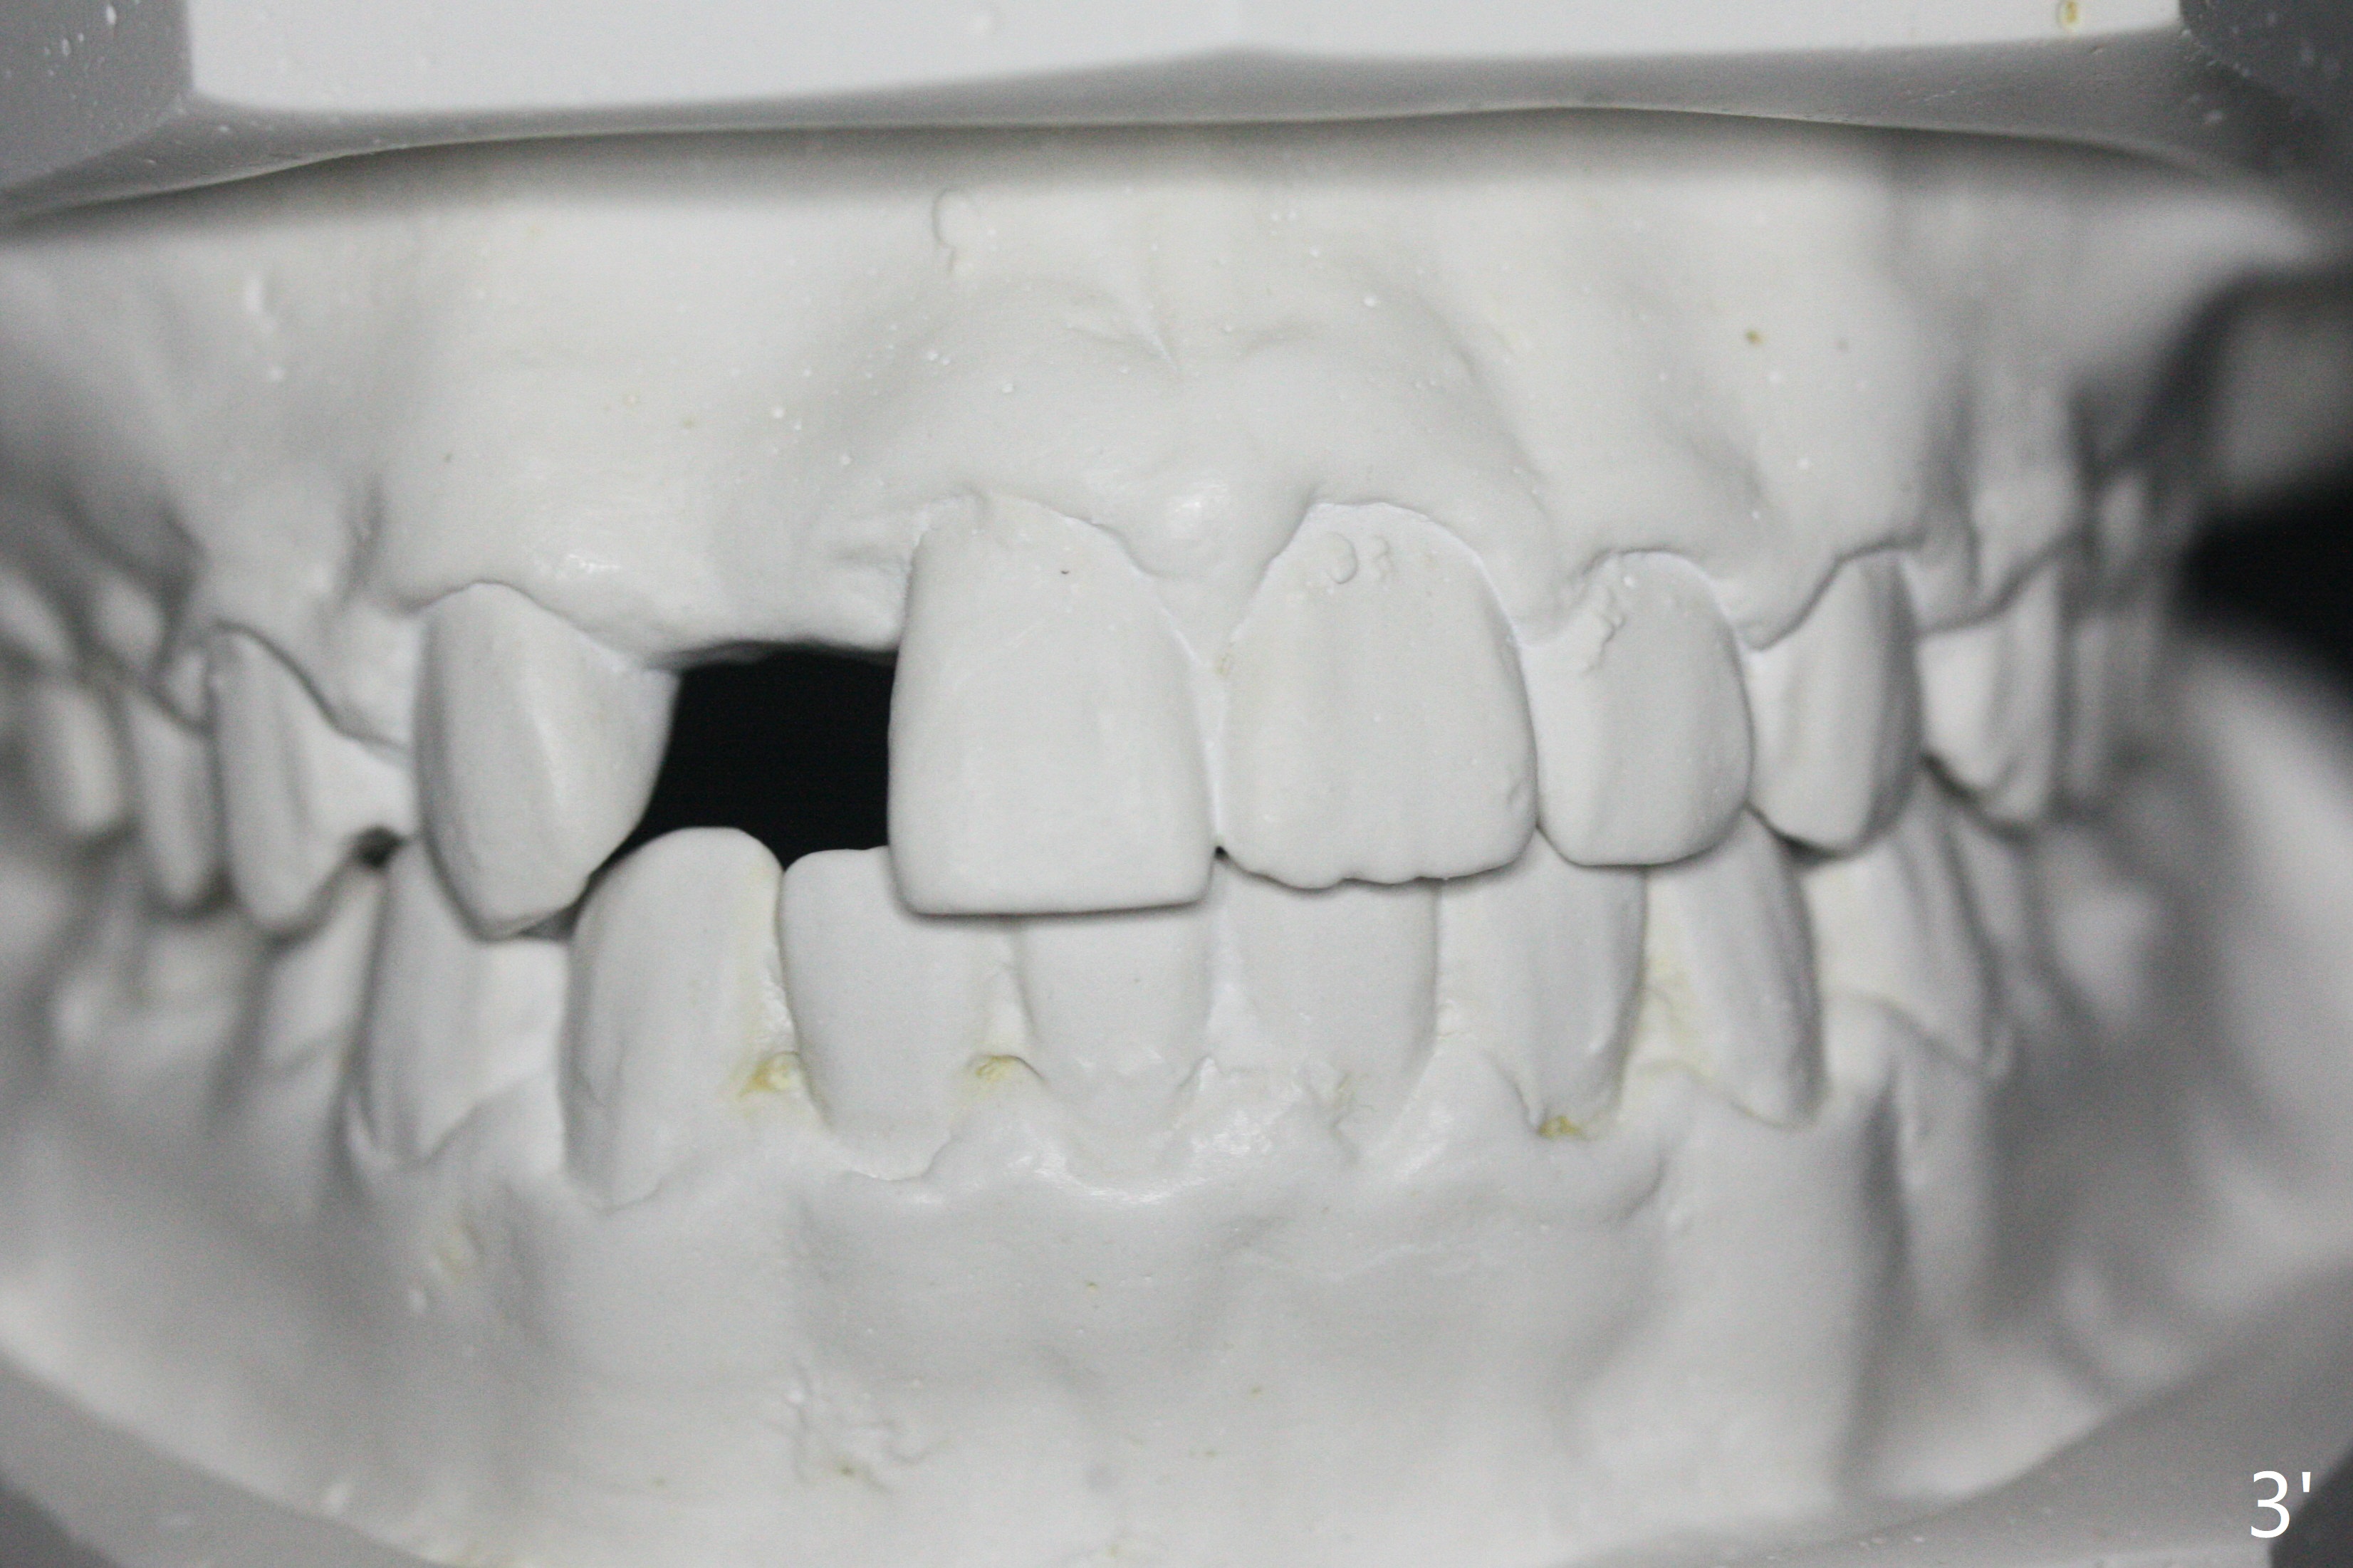

A 15-year-old man finishes orthodontic treatment for congenital missing lateral in 13 months. Molar Class I relationship remains the same (Fig.1,2,4,5). The upper diastemata mesial to 4s (Fig.4,7") close with correction of the upper midline deviation (Fig.2'-4'). The kid is unpleased with the elongated UR1 (Fig.2',3'). In fact it is a preexisting condition (Fig.2 arrow, 2"), but bracket placement at UR1 should have been overcorrected (incisal placement, Fig.3"). The intrusion should be done (Fig.4") before closure of the diastemata, since anchorage may be weakened when the separation between UR1 and 3 increases by using open coil spring. To prevent immediate relapse of the diastema between the upper central incisors, a fixed retainer is placed lingual before debracketing (Fig.6,6',6").